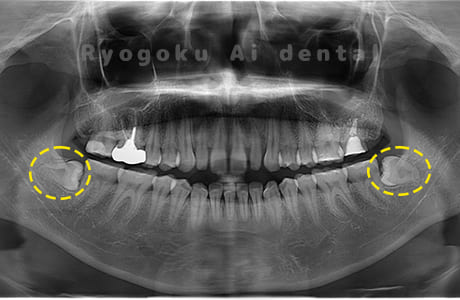

Case02

- 原因

- 下顎の水平埋伏智歯

- 治療内容

- 下顎の水平埋伏智歯を抜歯

<リスク・副作用>

手術後は痛み、腫れ、痺れなどの副作用が生じる場合があります。